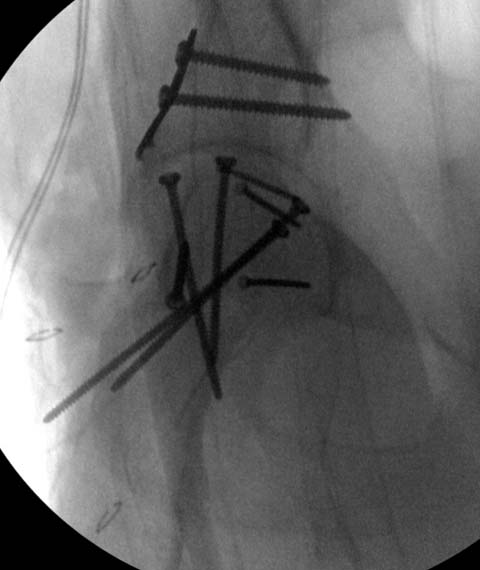

Здесь клинические примеры: Первый случай передний доступ, второй с ICP

monitor Flipp Trochanteris

и с переломом заднего края.